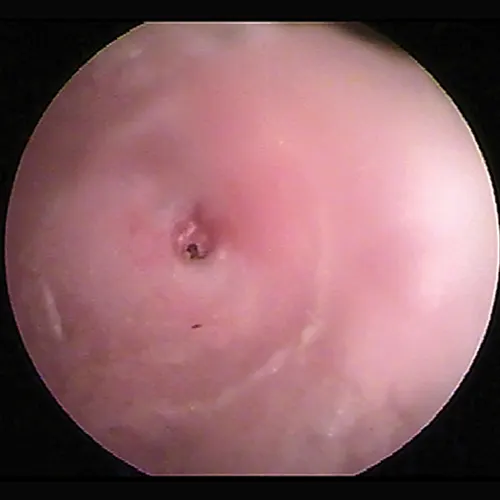

Because the normal pars tensa is translucent, the bulla cavity can be seen when enough light (using a video otoscope) transilluminates the bulla. In otitis media, fluid, if present, can be seen behind the eardrum in the form of bubbles, blood, serum, or pus. Increasing pressure from exudate accumulation can cause the pars tensa to bulge outward. Both of these conditions result in marked pain; pressure must be relieved by myringotomy. Any tissue mass in the middle ear will obscure the ability to view the middle ear (Figure 15). Occasionally, in cats, a middle ear polyp can be seen through the eardrum as a fleshy mass in the bulla.

Otoscopic image of pink mass with red striping seen behind ear drum.

FIGURE 15

Tissue mass behind the eardrum. Note the malleus bone in the pars tensa, indicating the mass is behind the eardrum.